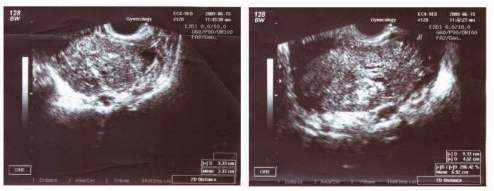

Nynější onemocnění: Pacientka přichází k potvrzení gravidity na UZ v 9. gestačním týdnu. Při UZ vyšetření byl prokázán jeden živý plod, CRL12mm, ovárium vlevo obklopeno anisochegenním útvarem o velikosti 9x5 cm, mírný ascites. Při vaginálním vyšetření byla hmatná za dělohou omezeně pohyblivá rezistence, neostře ohraničená. Pro vysokou suspekci na maligní etiologii odebrány (CA 125: 280 iu/ml, AFP a CA72-4 negativní)a provedeny stagingová vyšetření (RTG S+P a UZ epigastria negativní).